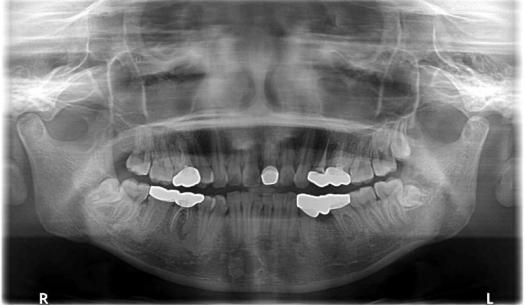

口内检查发现多颗烤瓷冠和三组烤瓷联桥(详见全景片)。

右侧磨牙关系完全远中,左侧磨牙关系中性,前牙深覆合深覆盖,下牙列拥挤。全景片示:14、24、35缺失;16,26,36,46根尖周暗影,18,28,38,48正位萌出;多生磨牙29,39,49可见。